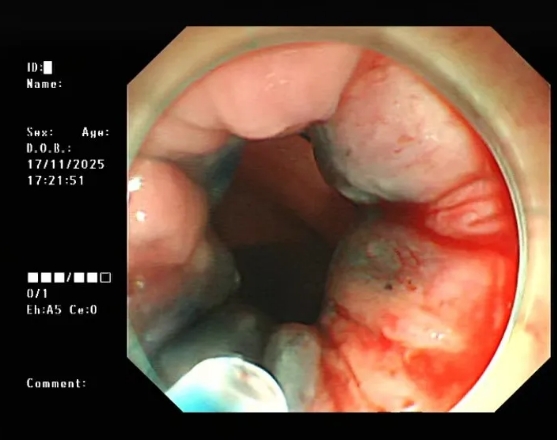

近期,洛阳白马医院消化内科接诊了一位患者。女性,80岁,以突发皮肤巩膜黄染1周入院。入院时可见老人家全身皮肤、巩膜中度黄染。入院后诊断胰头占位,梗阻性黄疸,肝功能异常等。考虑患者高龄,心肺功能较差,与家属沟...